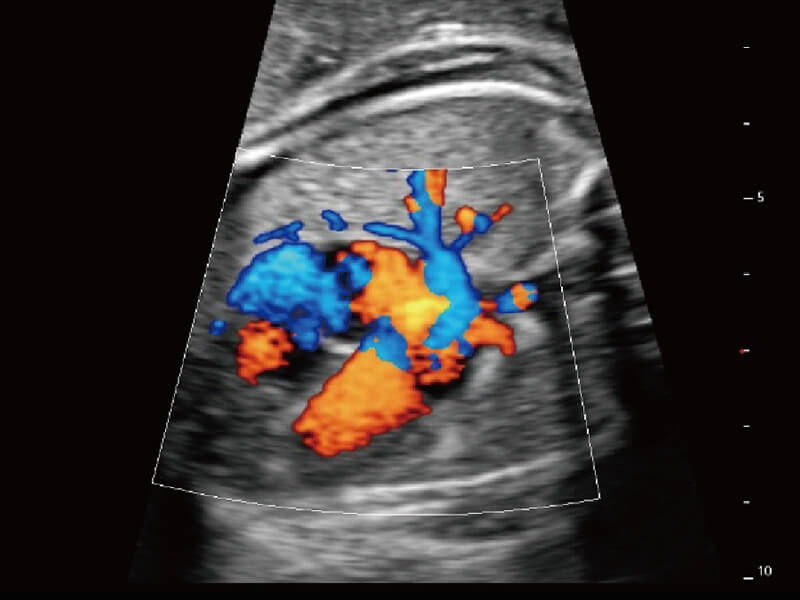

成像功能

性能优异的硬件架构,极大提升超声系统的运行效率和数据处理能力。相比以往超声成像系统,Wis+平台为您带来极快的响应速度和成像帧频,提升检查流畅度。